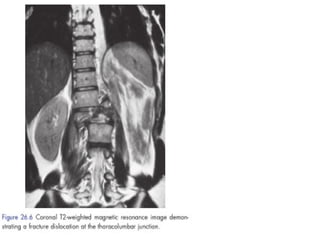

Thoracolumbar spinal fractures (T11–S1)

The thoracolumbar junction is especially prone to injury. This

can vary from a minor wedge fracture to spinal dislocation.